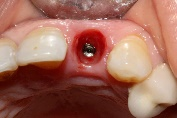

After implant placement (Figure 9), the primary stability of the implant was satisfactory (greater than 35N), the provisional abutment was fixed (Figure 10) and a post-operative retroalveolar radiograph was taken for radiological control of the implant and adaptation of the provisional abutment (Figure 11).

PMMA resin was placed around the provisional abutment, and the occlusion was checked to ensure that the provisional prosthesis was underbite (Figure12).

Figure 9. Drilling sequence